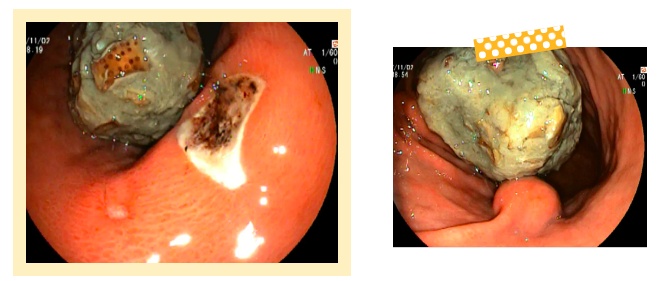

△某患者食用大量山楂后产生的胃结石

医生表示,是否产生结石在很大程度上受个体差异和食用量影响,并且通过脱涩处理的山楂,鞣酸含量会降低。对健康的人而言,即使产生少量鞣酸蛋白沉淀物,也可随着胃肠蠕动排出体外。但秋冬季,进食高鞣酸食物仍需多加注意。